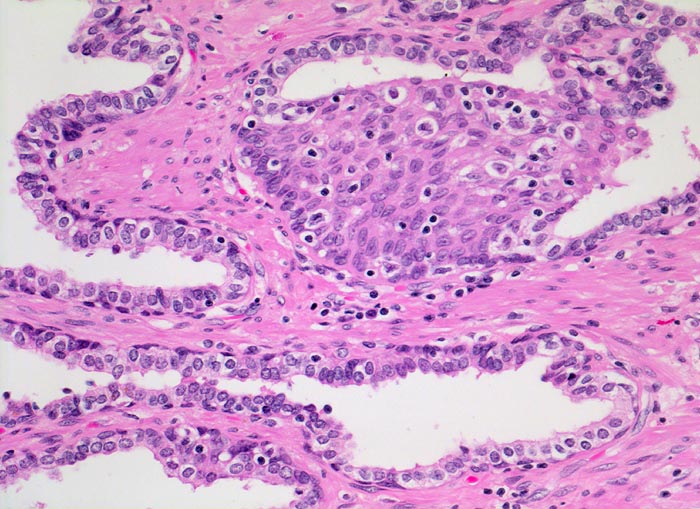

Normale Prostatadrüsen mit Basalzellhyperplasie

Das normale Prostataparenchym besteht aus Paketen grösserer Drüsen eingebettet in glatte Muskulatur. Das Epithel der tubuloalveolären Drüsen ist ein- bis mehrreihig und weist eine durchgehende Schicht flachgedrückter Basalzellen auf. Nicht selten kann eine fokale Hyperplasie dieser Zellen nachgewiesen werden. Die Epithelzellen haben mittelgrosse runde bis ovale Kerne mit winzigen Nukleolen und reichlich Zytoplasma.

Die Abwesenheit der Basalzellschicht ist eines der verlässlichsten Kriterien zur Diagnose eines Adenokarzinoms. In verschiedenen benignen Läsionen ist die Basalzellschicht fragmentiert, fehlt aber praktisch nie vollständig. In Zweifelsfällen kann die Basalzellschicht immunhistochemisch nachgewiesen werden.